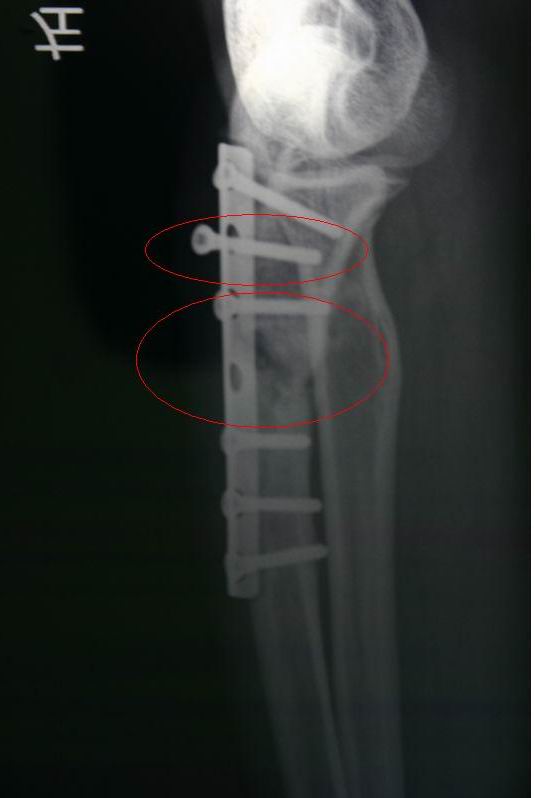

我可怜的手,再也不能开摩托了,也不能玩激烈的户外活动。

前年十月骨折,镶了钢板,手术7个月后跑西藏,现在有点移位,一颗锣丝松了。。骨头现在还没长好。。再长不好又要开刀。。现有什么玩意能帮忙骨头快速生长。谢谢